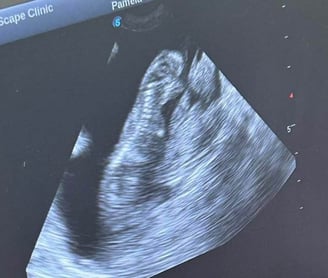

Echoskopija (ultragarsinis tyrimas)tai vaizdinės diagnostikos tyrimas leidžiantis įvertinti pilvo organų struktūras bei būklę.

Pasitelkiant echoskopu galima diagnozuoti vaikingumą, inkstų, kepenų, tulžies pūslės ligas, gimdos uždegimą, auglius, šlapimo pūslės akmenis ir kitus reikšmingus pokyčius.